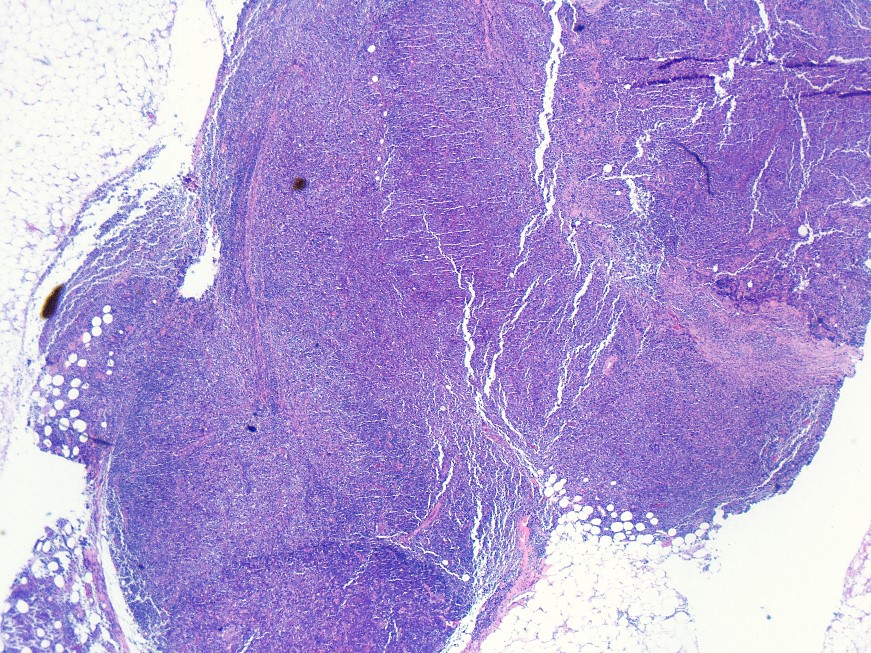

Picture560 yo M w/ generalized LAD & mediastinal mass. EBUS-FNA of R level 2 mediastinal LNs.

What's the...